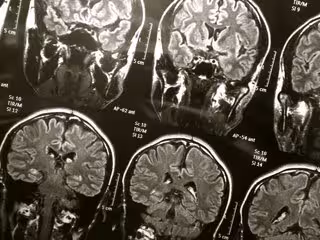

Cerebro

FLICKR/WYINOUE - Archivo